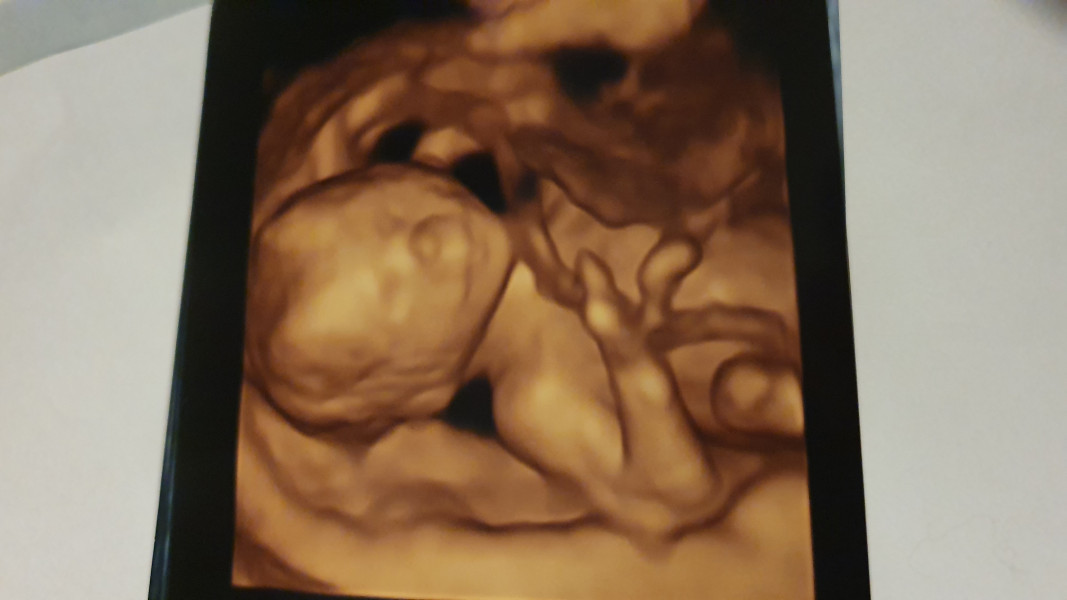

Should i be worried about my baby's development from this scan photo

Hi. I got a private 16 week scan to find out the gender. It was a very quick scan and i didnt ask any questions. Im now obsessing over the photos due to the hand is this normal? Should i contact my hospital to do a scan and check for abnormalities

3D and 4D scans can be blurry and unreliable before 26weeks, a time when the babies features are more defined and the tissue is denser/more refined. The echoes that make up the image are easily distorted and blur together if your baby is moving while the imaging is being done or if you shifted position or were breathing deeply/rapidly when the image was taken. Also, the new structure of babies features and lower density at these earlier scans (like the one you had) can make the images blurry as the echoes don't bounce very well.

DD looked like she was made of melted wax when the technician turned on the 4D. Even when they're nearly full term they look weird on those things, but at 16 weeks they look terrifying.

Remember that the baby is continually moving, so the images often reflect that with things looking stretched.

I always think 4D scan pictures seem very distorted and like melted candles, it's apparently something to do with the baby moving around so you get the movement included as blurriness in the image. If the sonographer had seen anything that caused them concern surely they'd have told you to get in touch with your midwife?